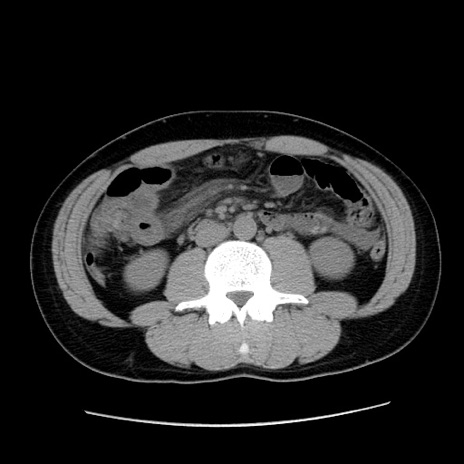

症例36(横断像)

【症例】20歳代 男性

【主訴】心窩部痛

【現病歴】今朝より上腹部痛あり。一旦軽快していたが再度出現したため救急要請。昨日夕に白身の魚を含む刺身を食べた。

【身体所見】BP 136/89mmHg、HR 74/min、BT 37.0℃、腹部:膨満、軟、心窩部に圧痛あり。反跳痛なし、筋性防御なし、腸雑音やや亢進あり。

【データ】WBC 17700、CRP 0.48